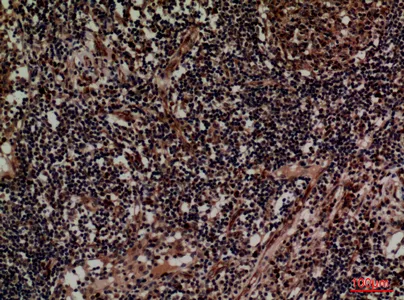

CD1D Rabbit Polyclonal Antibody

Cat: APRab08263

Size1:50μl Price1:$118

Size2:100μl Price2:$220

Size3:500μl Price3:$980

Size2:100μl Price2:$220

Size3:500μl Price3:$980